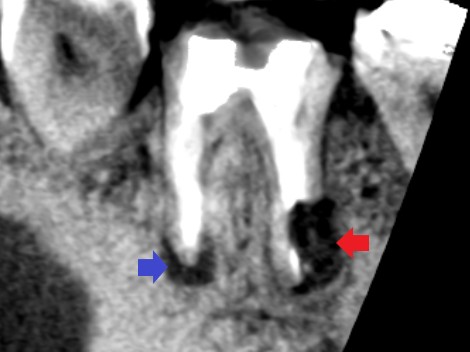

精密再根管治療1年後の下顎第一大臼歯の矢状断のCT画像です。近心根と遠心根にみられた膿の影が消えてきています。赤い矢印の先は、手術を失敗していた遠心根です。

精密再根管治療1年後の下顎第一大臼歯遠心根の冠状断のCT画像です。赤い矢印の先に歯根膜ができ始めているようにみえます。